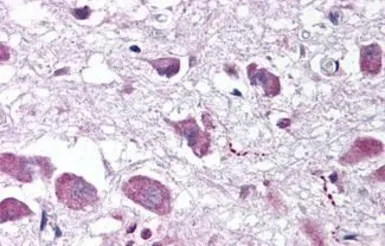

Orexin A antibody

Cat. No. GTX85868

ApplicationsIHC-P IHC-Fr ELISA

ReactivityHuman